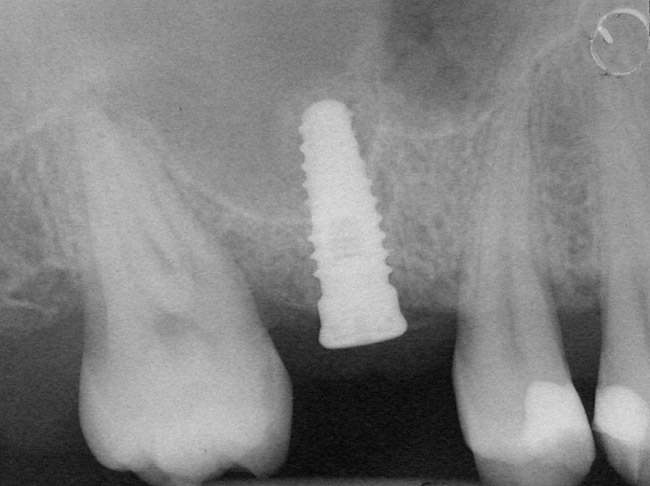

Figure 4  Implant positioning; the radiograph taken 4 weeks after placement confirmed good primary stability.

Figure 4